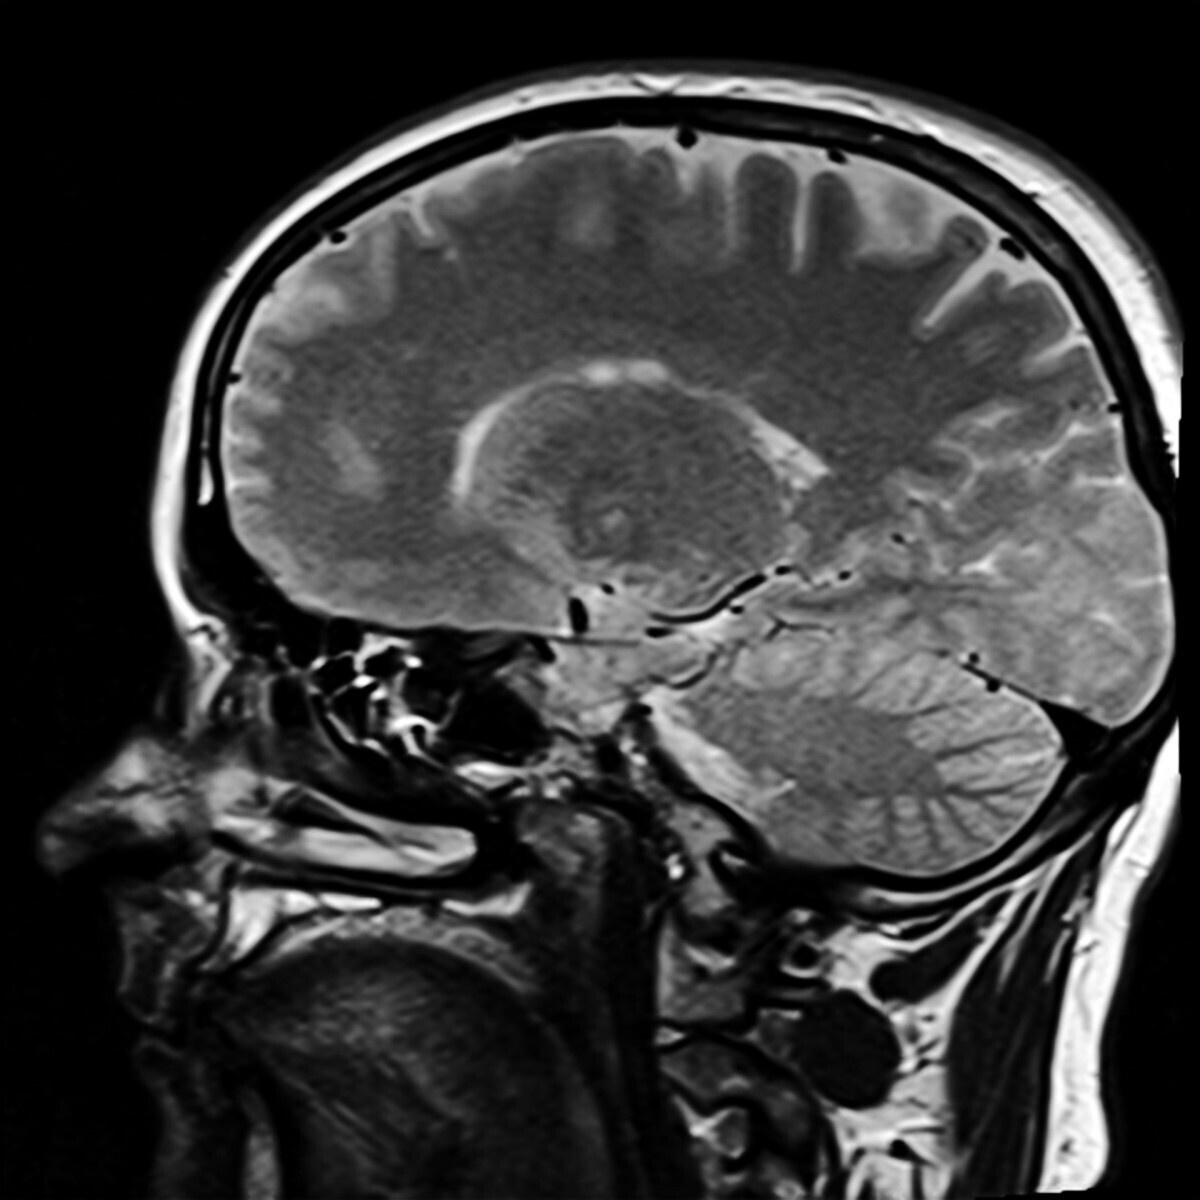

Исследователи из нижегородского Университета Лобачевского (ННГУ) разработали онлайн-платформу «Калькулятор когнитивного биологического возраста», которая на основе пяти коротких тестов оценивает память, внимание, скорость реакции и цветовосприятие. В основе лежит модель машинного обучения Cognitive-Age-V, обученная на данных более 1800 человек. Система уже внедряется в практику медицины здорового долголетия «Росатома» и ФМБА.

Разработка позволяет вычислить разницу между хронологическим и когнитивным возрастом. У пациентов с деменцией система зафиксировала ускоренное старение мозга в среднем на 15,4 года, а у людей с умеренными когнитивными нарушениями — на 7,6 года. Используемый SHAP-алгоритм показывает, какие именно функции (скорость распознавания цвета, устойчивость внимания или моторная реакция) дали основной вклад в отклонение.

Как отметил директор НИИ биологии старения ННГУ Михаил Иванченко, снижение скорости реакции, ухудшение памяти и цветового зрения может быть связано не только с естественным старением, но и с развитием деменции, последствиями диабета, депрессии или нарушений сна. Бесплатный инструмент доступен любому пользователю, что позволяет проводить персонализированную профилактику нейродегенеративных заболеваний.